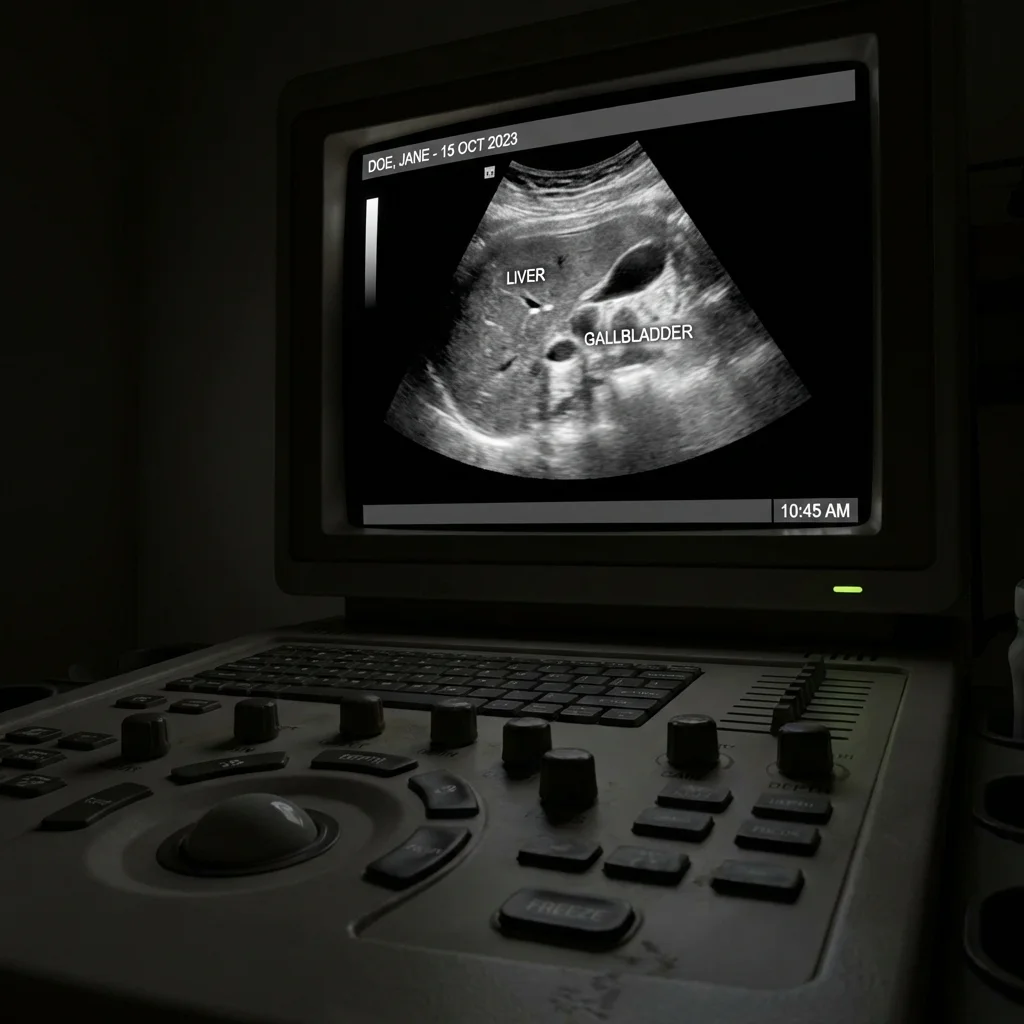

Οι υπέρηχοι είναι μια ασφαλής μέθοδος απεικόνισης που χρησιμοποιεί ηχητικά κύματα υψηλής συχνότητας για την παραγωγή εικόνων των εσωτερικών οργάνων του σώματος.

Επειδή δεν χρησιμοποιούν ιοντίζουσα ακτινοβολία (όπως οι ακτίνες Χ), είναι απόλυτα ασφαλείς και κατάλληλοι για όλες τις ηλικίες, συμπεριλαμβανομένων των εγκύων και των παιδιών.

Ο ιατρός εφαρμόζει ειδικό υποαλλεργικό τζελ και σαρώνει την περιοχή με τον ηχοβολέα. Η διαδικασία είναι εντελώς ανώδυνη.

Η εικόνα εμφανίζεται σε πραγματικό χρόνο στην οθόνη και ο ιατρός σας εξηγεί τα ευρήματα. Η γνωμάτευση δίνεται άμεσα.